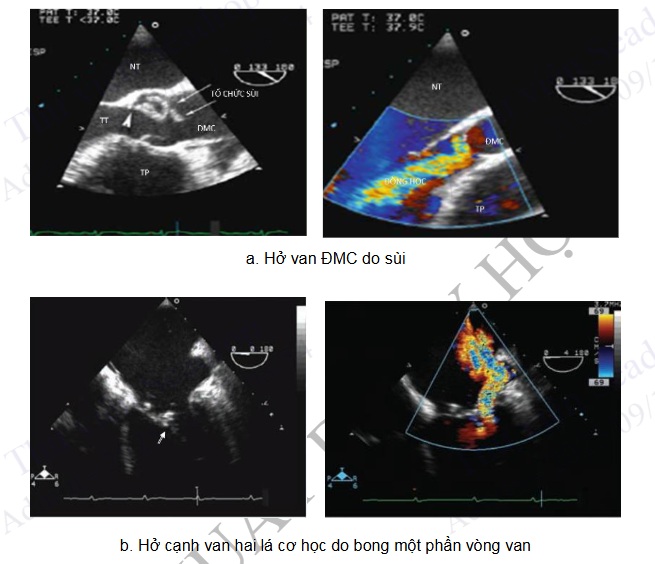

Chẩn đoán bệnh: + Tách động mạch chủ + Chẩn đoán viêm nội tâm mạc nhiễm khuẩn và các biến chứng của bệnh trên van tim tự nhiên và van nhân tạo + Xác định huyết khối buồng tim (tiểu nhĩ trái, tâm thất, van tim và động mạch chủ). + Quan sát các khối u tim + Đánh giá các bệnh tim bẩm sinh.

Hình 4.83. Một số tổn thương trên siêu âm tim qua thực quản